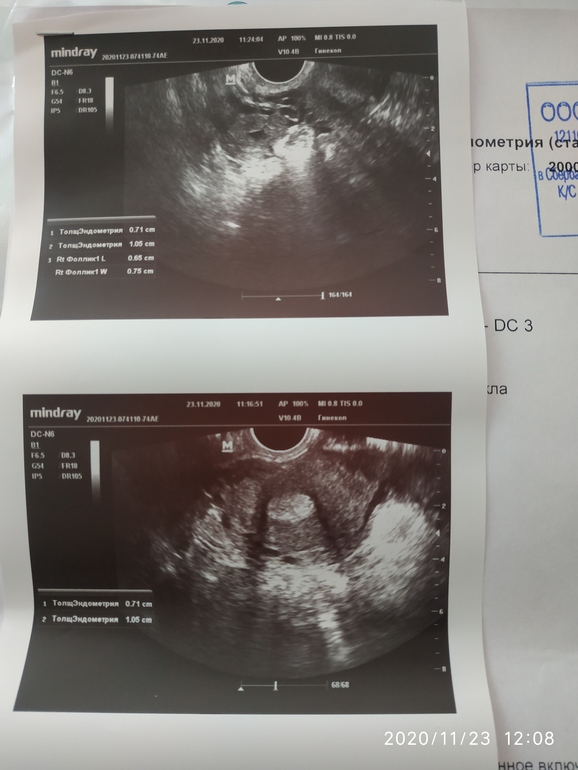

Может это ЖТ уже? Ну либо ДФ ушёл в регресс, а снимок есть с узи?

есть конечно

Что-то я здесь не вижу этого включения, про которое в заключении написано. Вообще сейчас увидела, что у Вас есть жидкость в позадиматочном пространстве, мне кажется, у Вас была уже овуляция.